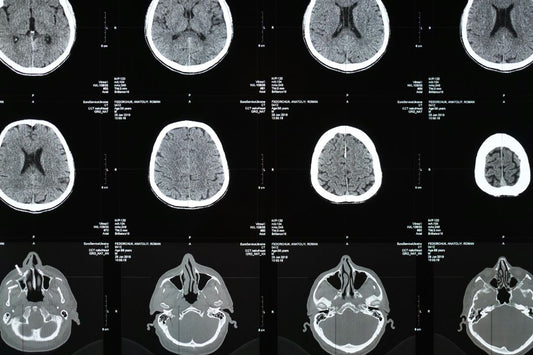

The Anatomy of a CT Scanner: How Every Part Pla...

From mechanical components to advanced software systems, every piece of a CT scanner is purposefully designed and carefully integrated to produce the highest quality images. A sophisticated machine that relies...

The Anatomy of a CT Scanner: How Every Part Pla...

From mechanical components to advanced software systems, every piece of a CT scanner is purposefully designed and carefully integrated to produce the highest quality images. A sophisticated machine that relies...